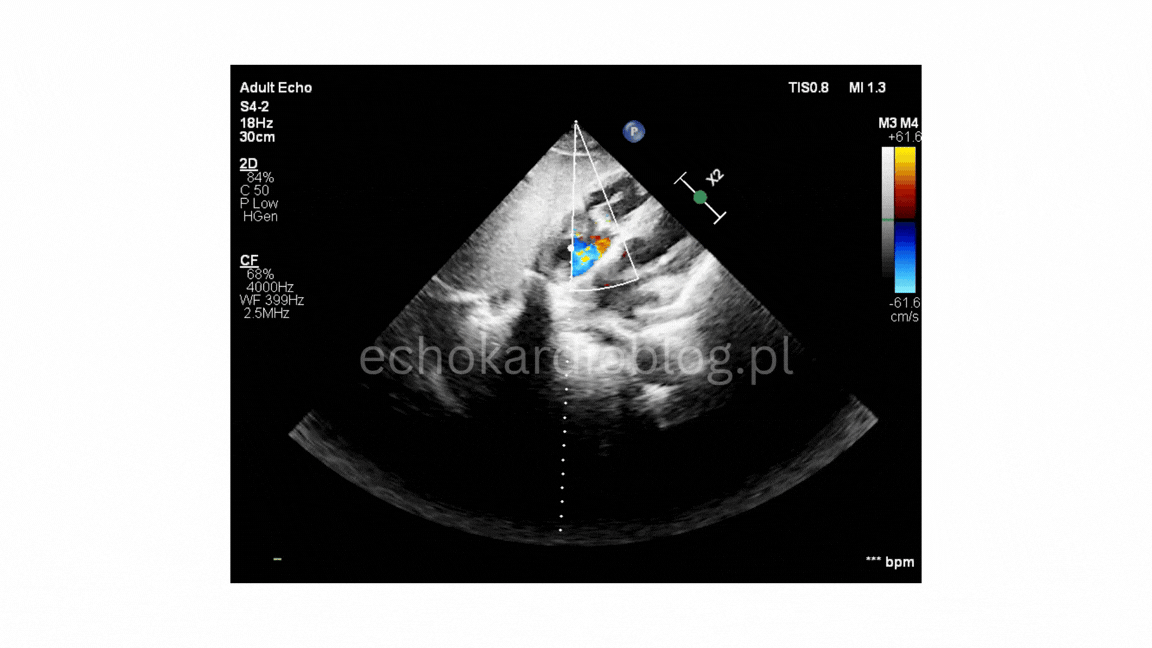

w projekcji – podmostkowej 4 jamowej uwidoczniono wegetacje na zastawce trójdzielnej i mitralnej

projekcja podmostkowa 4 jamowa- umiarkowana niedomykalność trójdzielna